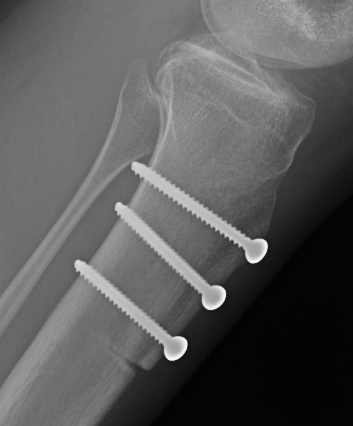

Tibial tuberosity Osteotomy

www.boneschool.com/tibialtuberosityosteotomy

Options

Medialization / Elmslie-Trillat

Anteromedialization / Fulkerson

Elevation / Maquet

Fulkerson Maquet

Tibial tuberosity osteotomy (TTO)